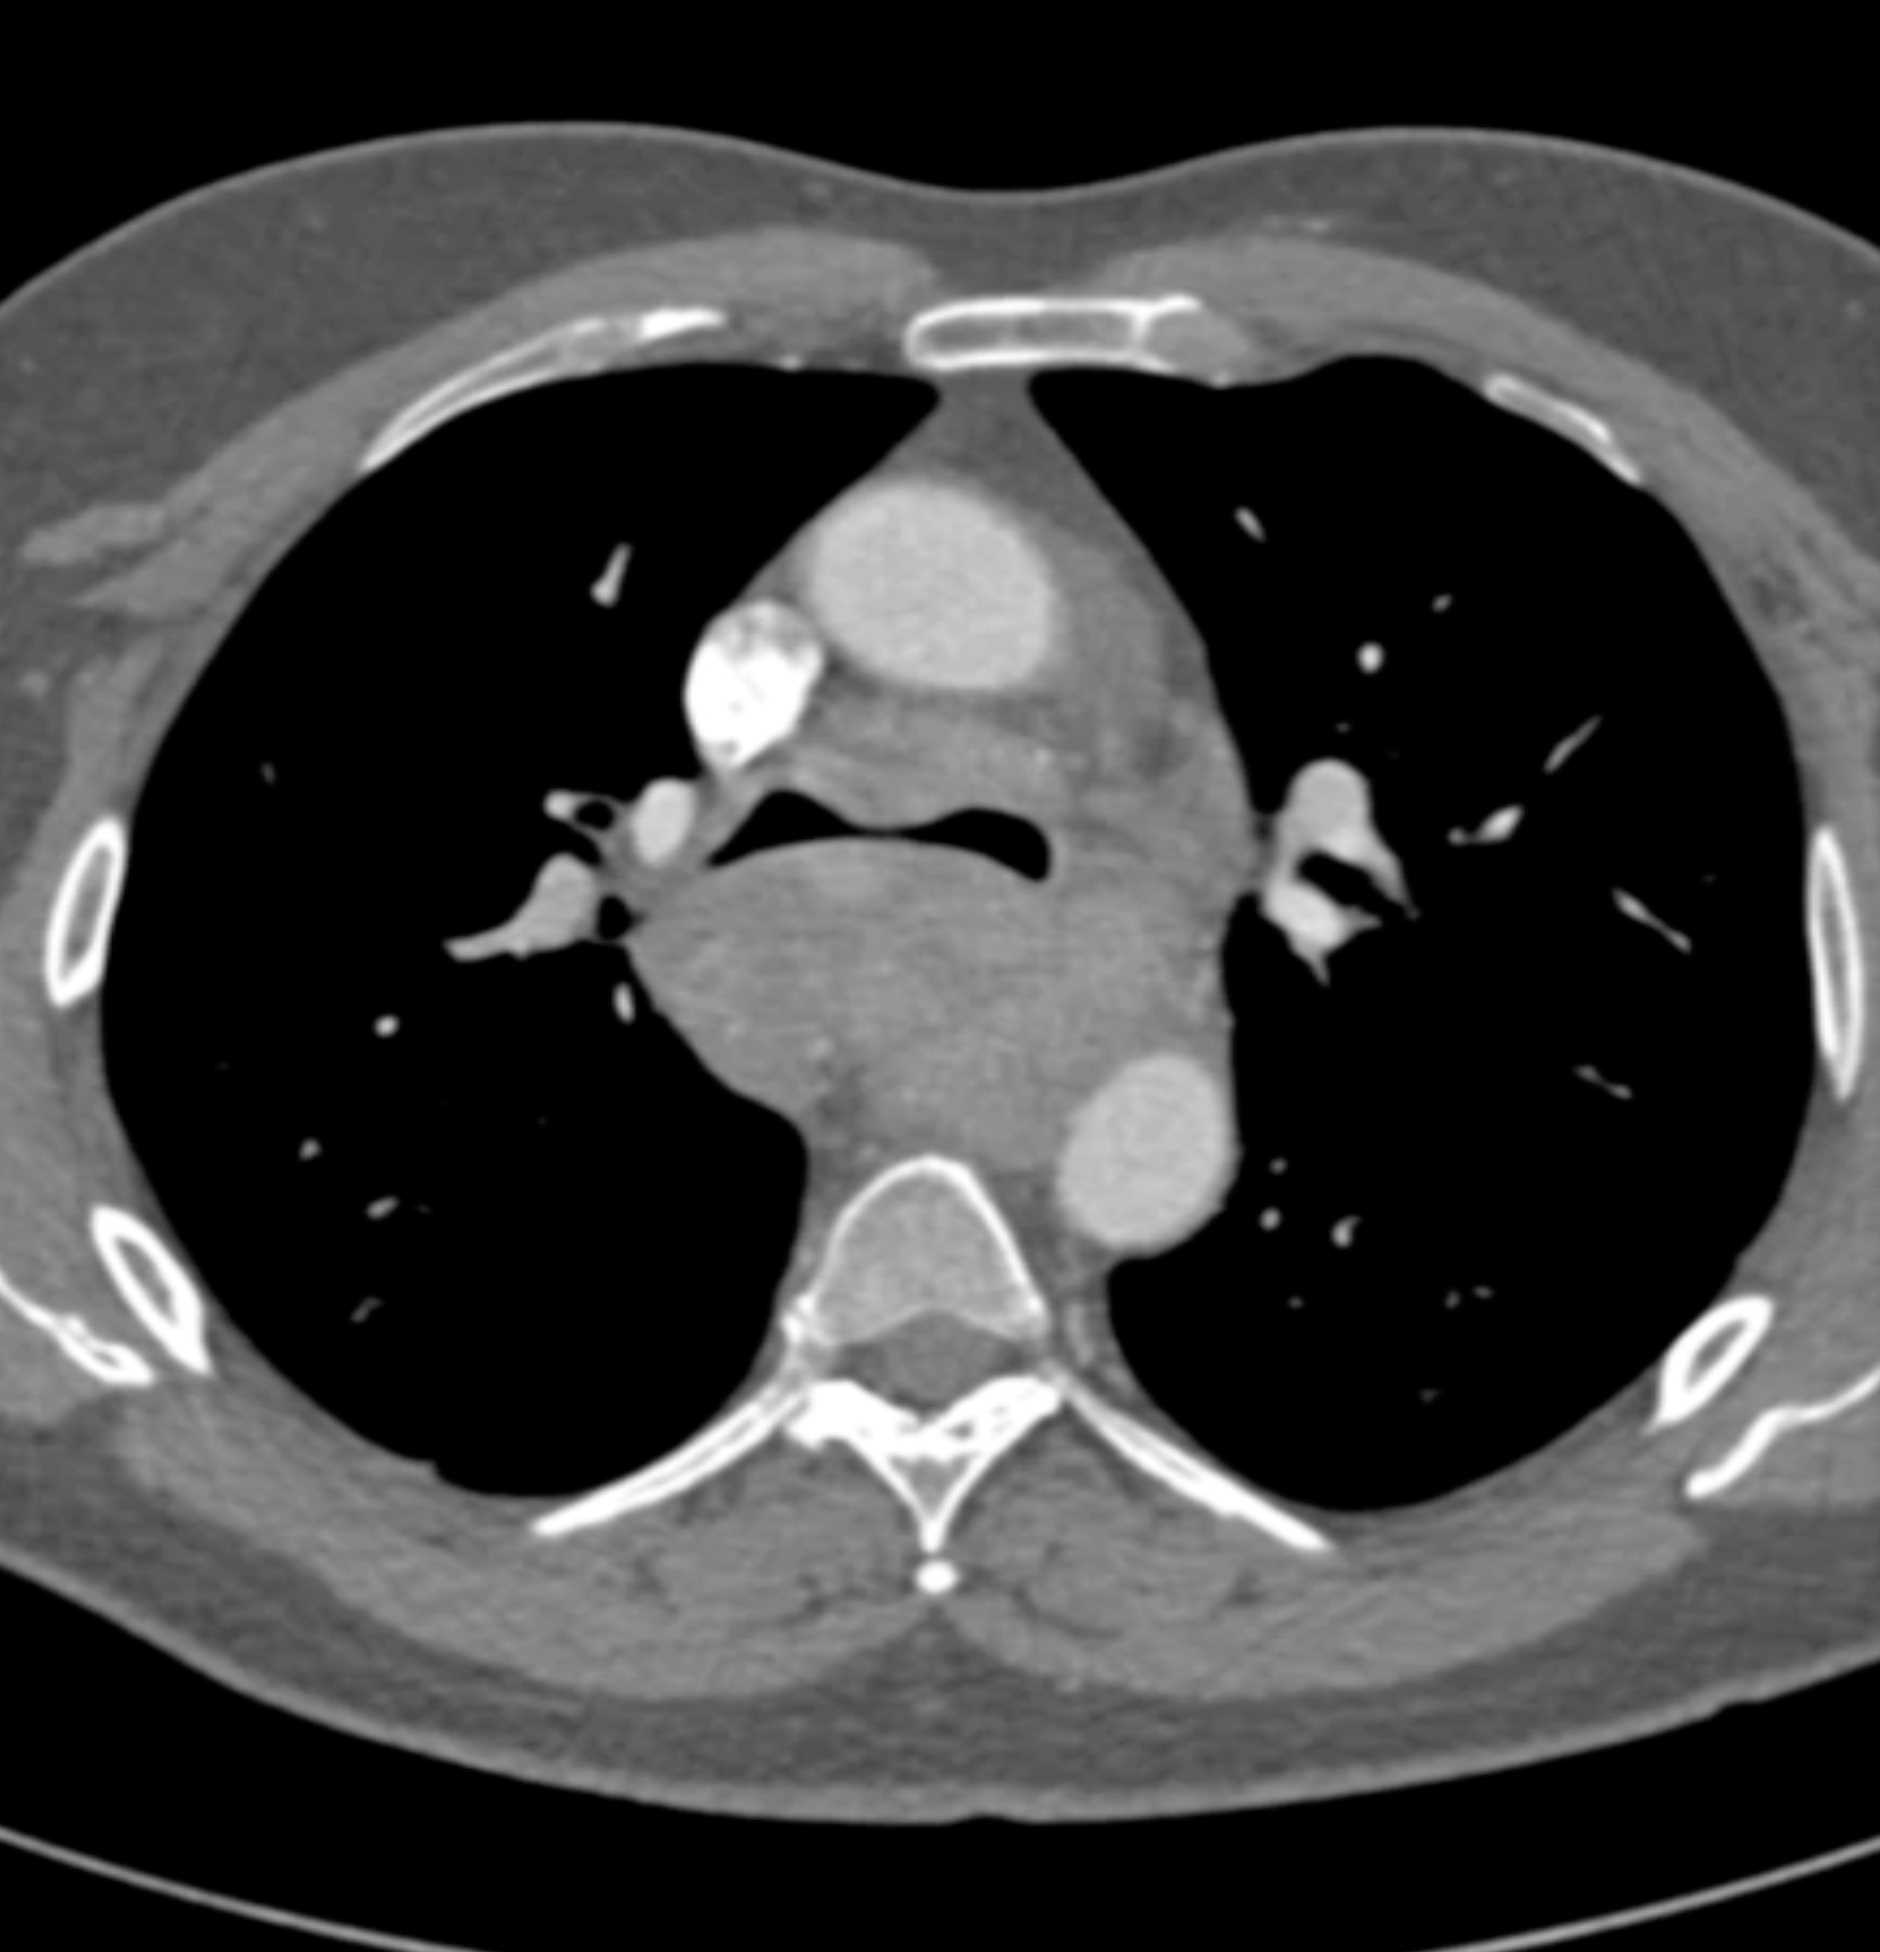

Fibrosing Mediastinitis